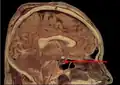

Гипо́физ (лат. hypophysis — отросток; синонимы: ни́жний мозгово́й прида́ток, питуита́рная железа́) — мозговой придаток в форме округлого образования, а также орган внутренней секреции, отвечающий за рост человека, он расположен на нижней поверхности головного мозга в костном кармане, называемом турецким седлом, вырабатывает гормоны, влияющие на рост, обмен веществ и репродуктивную функцию. Является центральным органом эндокринной системы; тесно связан и взаимодействует с гипоталамусом мозга.

Гипофиз располагается в основании головного мозга (нижней поверхности) в гипофизарной ямке турецкого седла клиновидной кости черепа. Турецкое седло прикрыто отростком твёрдой оболочки головного мозга — диафрагмой седла, с отверстием в центре, через которое гипофиз соединён с воронкой гипоталамуса промежуточного мозга; посредством её гипофиз связан с серым бугром, расположенным на нижней стенке III желудочка. По бокам гипофиз окружён пещеристыми венозными синусами.

Гипофиз на сагиттальном и корональном срезах МРТ с контрастным усилением